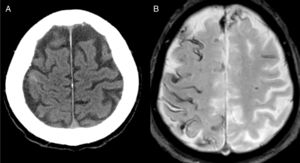

El diagnóstico más frecuente fue AAC (fig. 1) con un total de 8 casos. Tres fueron diagnosticados durante el año de seguimiento, uno de ellos por la recurrencia de HSAc y presencia de siderosis superficial en la RM, y los otros 2 por la aparición de un hematoma lobar.

Una posible explicación de que la causa más frecuente de HSAc sea la AAC es que, de forma similar a trabajos anteriores20,22,26, la mayoría de los casos recogidos tenían más de 60 años. Casi todos presentaron déficits neurológicos transitorios, recurrentes y estereotipados, también llamados amyloid spells. Se ha sugerido que la HSAc puede preceder en varias semanas a la aparición de un hematoma lobar3,4,27. De hecho 4 de nuestros pacientes sufrieron un nuevo sangrado en los meses siguientes al ingreso. Por tanto se debe ser cauto a la hora de prescribir antitrombóticos. Si el diagnóstico inicial es incierto, la realización de una RM cerebral diferida puede establecer el diagnóstico de AAC si aparecen nuevos sangrados o siderosis superficial4,5,24.